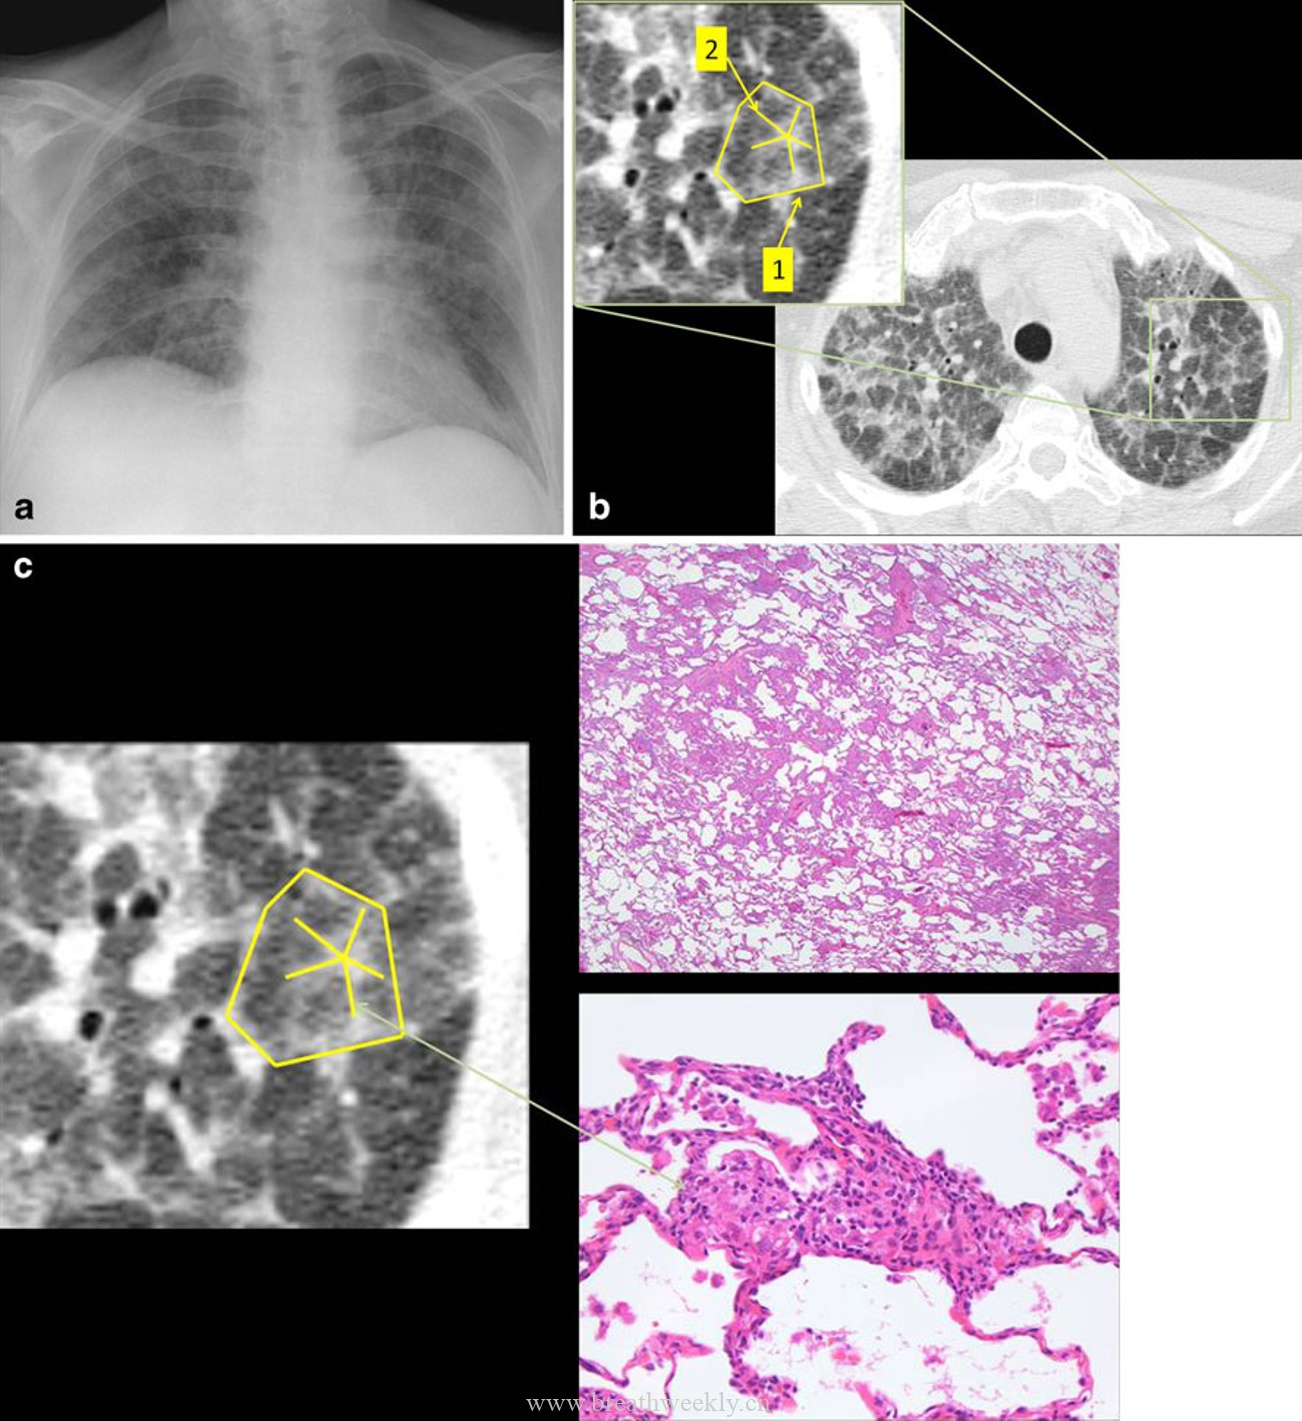

1. 肺泡蛋白沉积症(PAP)

典型表现:双肺中央地图样铺路石征,病理为肺泡内PAS阳性蛋白样物质沉积。线状影为腺泡周围型。